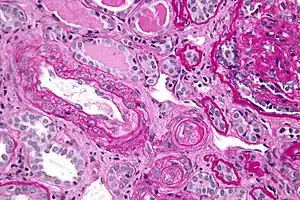

In the kidneys, chronic hypertension has a great impact on the kidney vasculature, leading to pathologic changes in the small arteries of the kidney. Affected arteries develop endothelial dysfunction and impairment of normal vasodilation, which alter kidney autoregulation. When the kidneys' autoregulatory system is disrupted, the intraglomerular pressure starts to vary directly with the systemic arterial pressure, thus offering no protection to the kidney during blood pressure fluctuations. The renin-aldosterone-angiotensin system can be activated, leading to further vasoconstriction and damage. During a hypertensive crisis, this can lead to acute kidney ischemia, with hypoperfusion, involvement of other organs, and subsequent dysfunction. After an acute event, this endothelial dysfunction has persisted for years.[10]